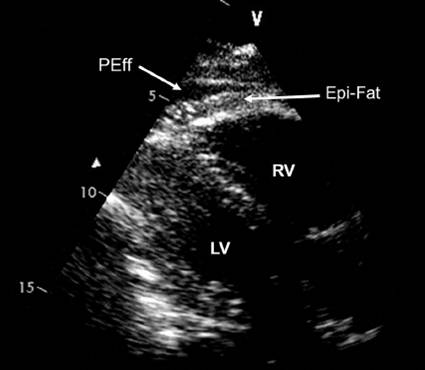

超声心动图

对心包厚度识别不是优势

cardiac tamponade and pulsus paradoxus